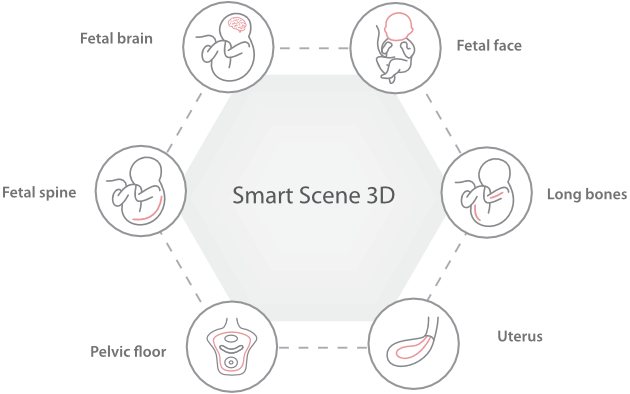

Nuewa I9? ??? ???? ?? ??? ?? ??? ???? ?? ??? ???? ???? ??? ?????. ??? ??? ??? ?? ????? ?? ???? ???? ???? ???? ??? ???? ??? ??? ???? ??? ???? ??? ?? ?????.